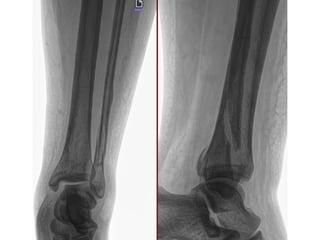

Diagnósticos: FRACTURA DIAFISIARIA TERCIO MEDIO DE TIBIA DERECHA EXPUESTA GA II AO 42A1C

Cirugía Proyectada: ASEO QUIRURGICO+ DESBRIDAMIENTO + REDUCCION CERRADA VS ABIERTA CON FIJACION INTERNA CON

COLOCACION DE FIJADORES EXTERNOS VS DCP 4.5 MM A TIBIA DERECHA

Material OSS Solicitado: NA

NOMBRE:MARTINEZ SANCHEZ IVAN NSS:39068715571M1987OR URGENCIAS A Edad: 32 AÑOS Comorbilidades: NINGUNA Fecha de la lesión: 13/09/25 Mecanismo de lesión: ACCIDENTE EN MOTOCICLETA Laboratorios: DENTRO DE NORMALIDAD Valoraciones: NA Diagnósticos: FRACTURA DIAFISIARIA TERCIO MEDIO DE TIBIA DERECHA EXPUESTA GA II AO 42A1C Cirugía Proyectada: ASEO QUIRURGICO+ DESBRIDAMIENTO + REDUCCION CERRADA VS ABIERTA CON FIJACION INTERNA CON COLOCACION DE FIJADORES EXTERNOS VS DCP 4.5 MM A TIBIA DERECHA Material OSS Solicitado: NA